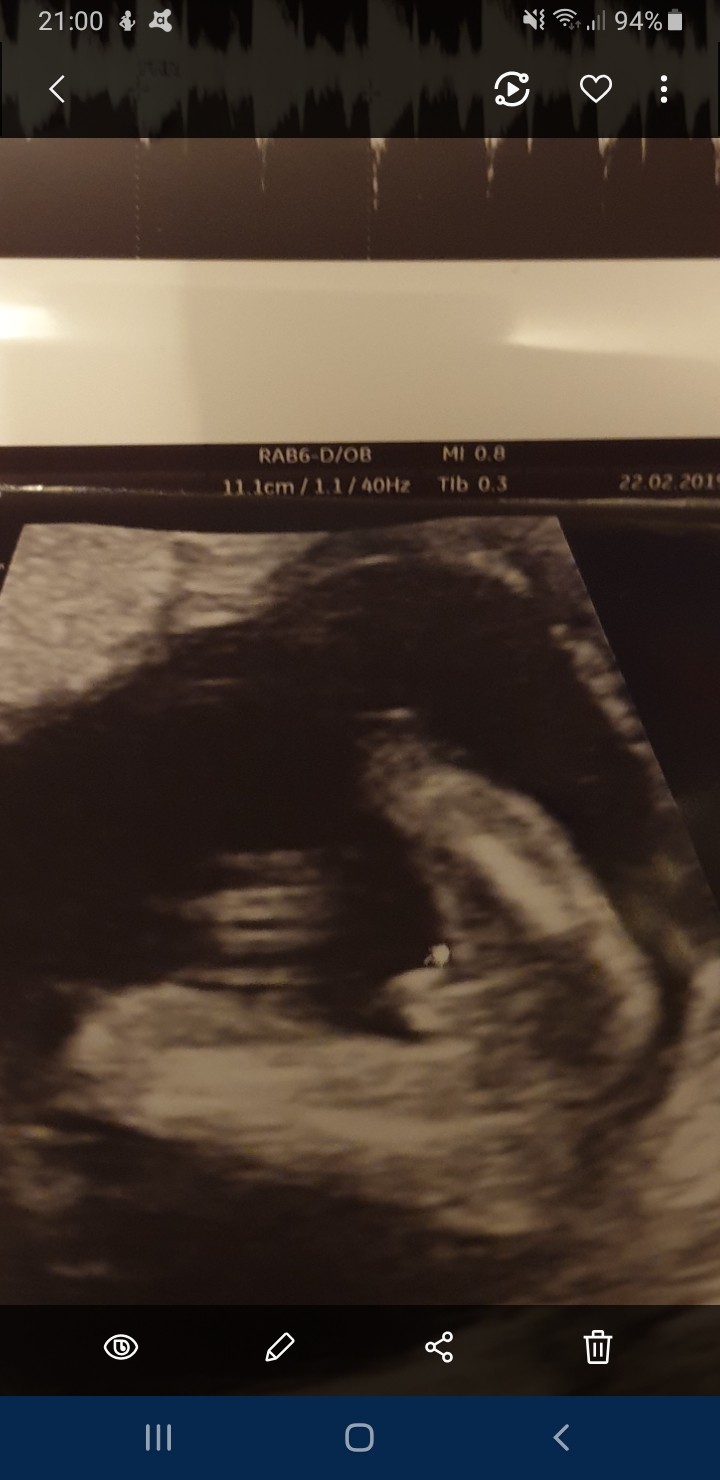

Hej dziewczyny chciałabym się upewnić co do płci czy aby na pewno chłopiec bo już zaczęłam zakupowe szaleństwo I nie chciałabym się później dowiedzieć że jednak będzie dziewczynka, a ja ubranka będę miała dla synusia. Dodam że wszystkie moje ciążowe objawy sugerowałyby dziewczynkę. Z góry dziękuję za odpowiedź

Screenshot_20190223-210030_Gallery.jpg

Hej dziewczyny chciałabym się upewnić co do płci czy aby na pewno chłopiec bo już zaczęłam zakupowe szaleństwo I nie chciałabym się później dowiedzieć że jednak będzie dziewczynka, a ja ubranka będę miała dla synusia. Dodam że wszystkie moje ciążowe objawy sugerowałyby dziewczynkę. Z góry dziękuję za odpowiedź Zobacz załącznik 946449

Jak dla mnie synek. A który tydzień ciąży jest na foto?